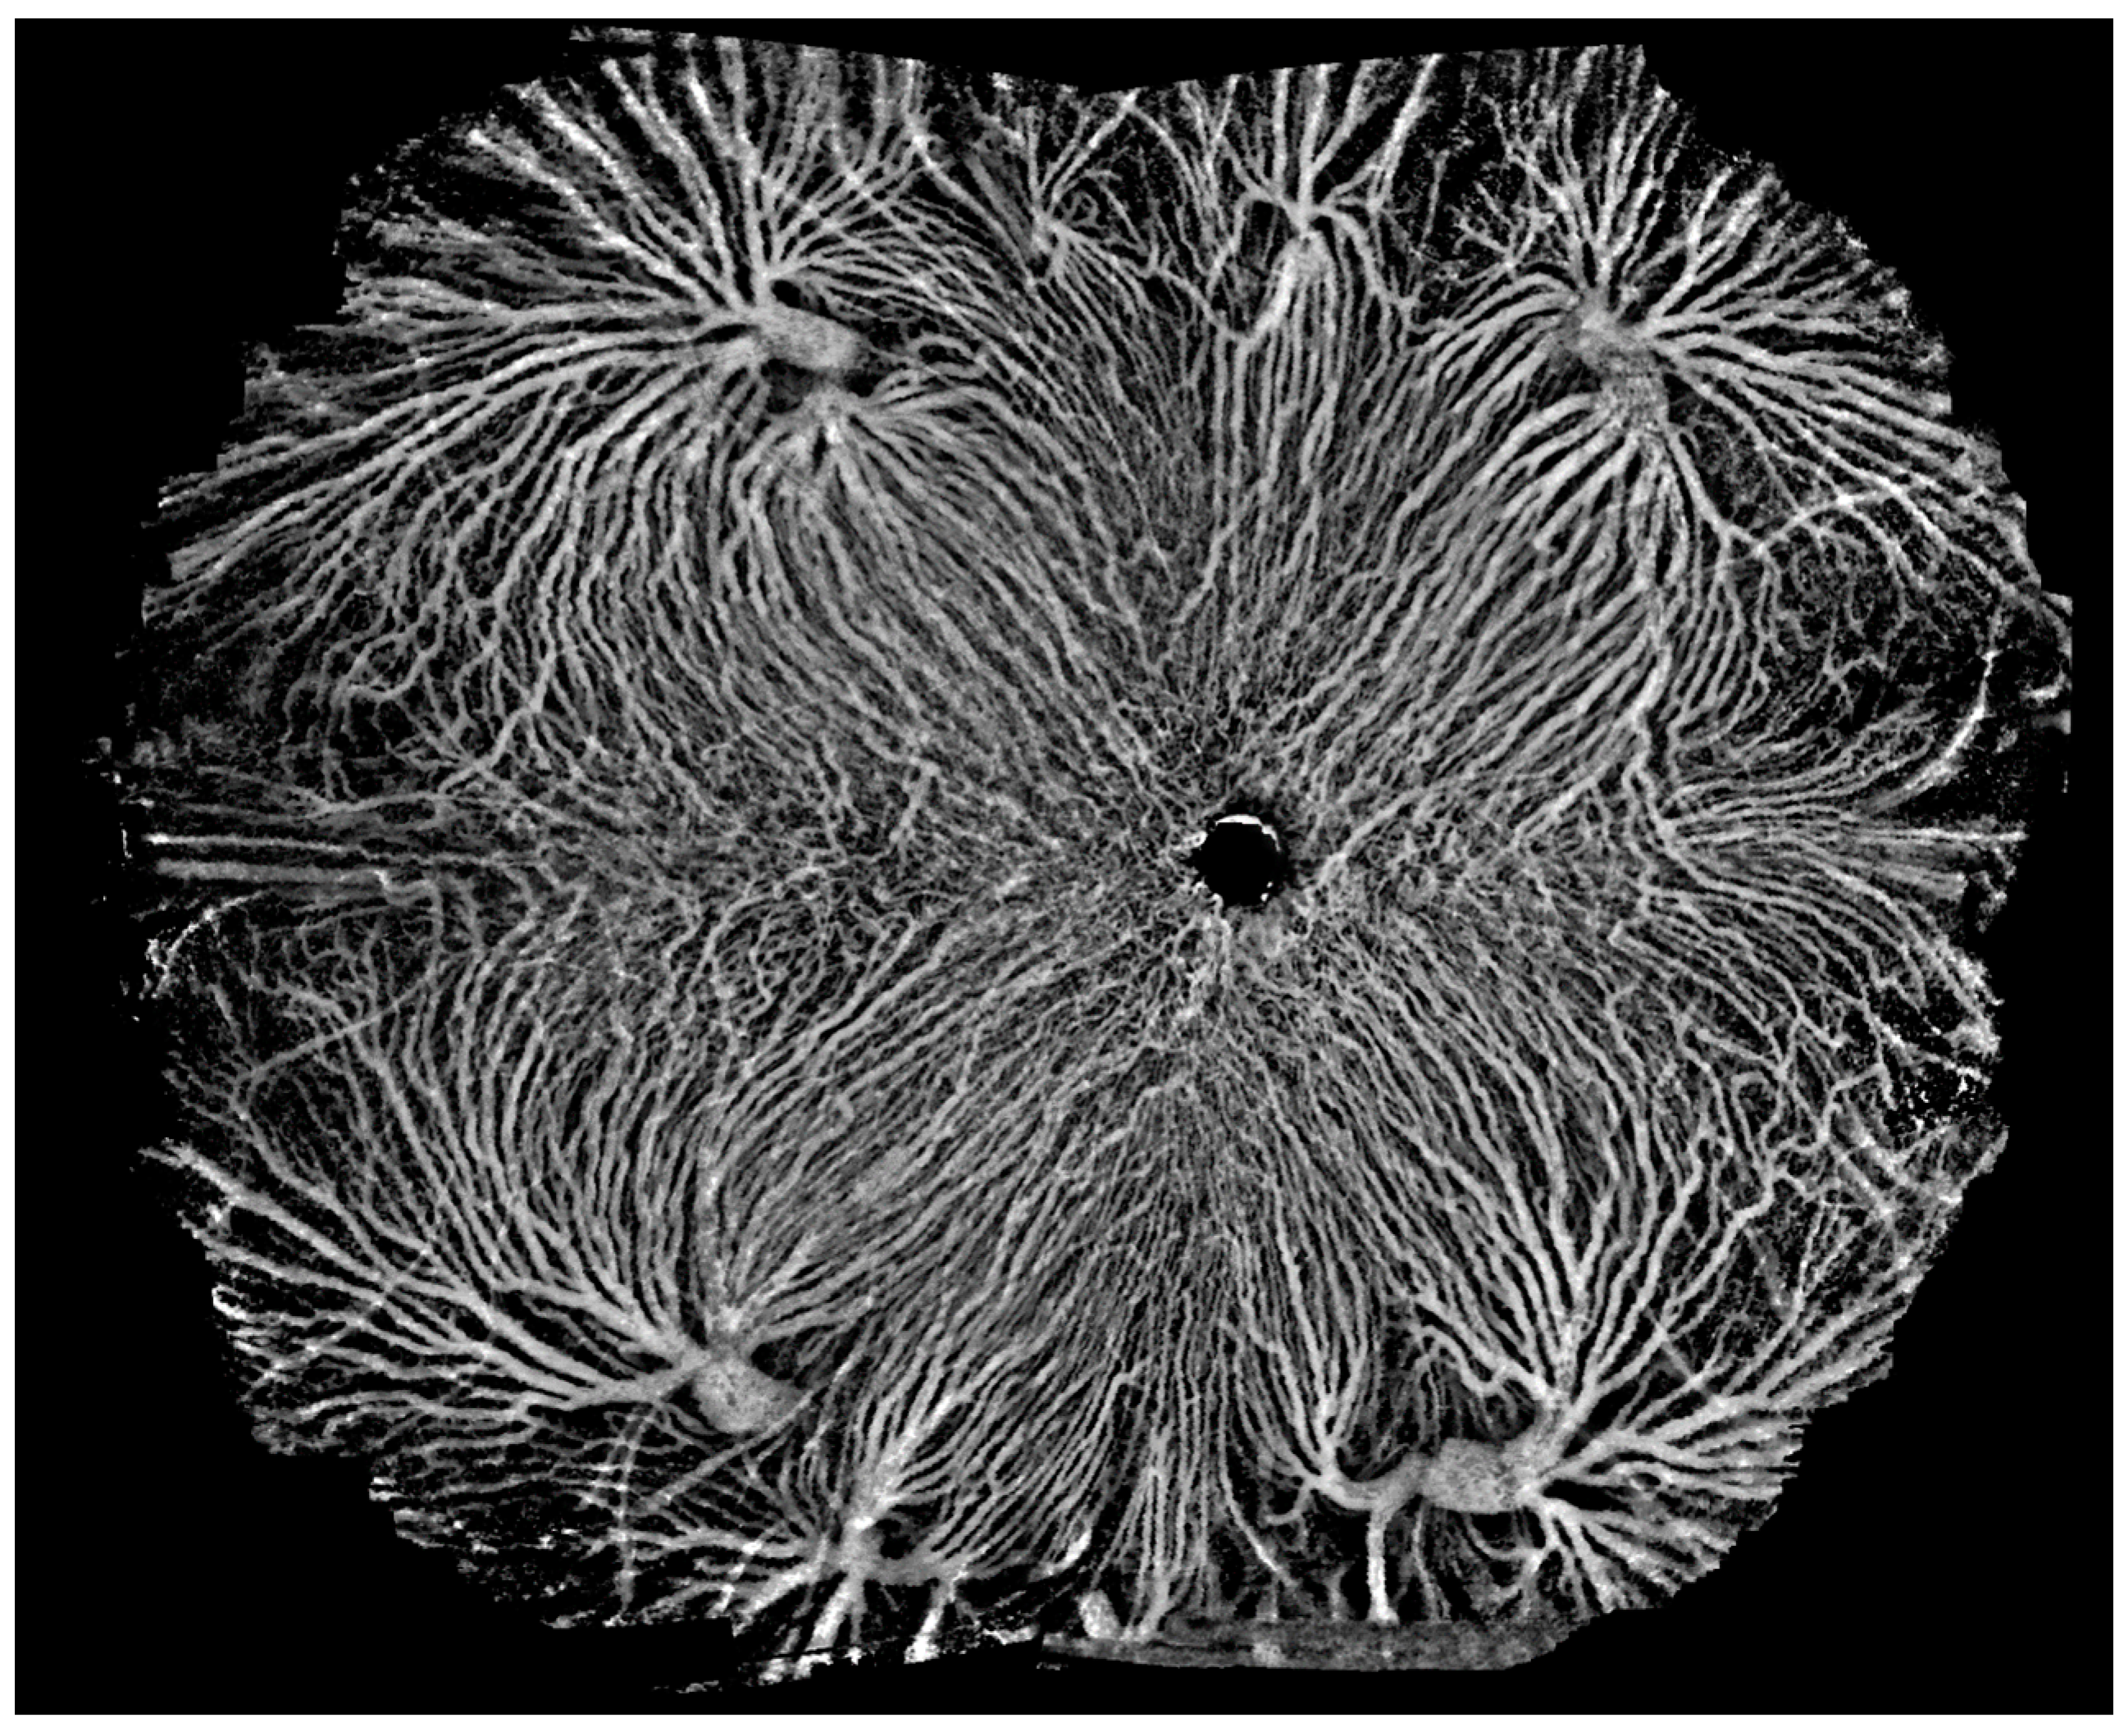

3.4. Ultra-Widefield OCTA

SS-OCTA modalities with a scanning frequency of 200,000 sweeps per second or more enable ultra-wide-angle imaging. Currently, SS-OCTA modalities with a scanning frequency of 400,000 sweeps per second can yield an image of 29 × 24 mm (inner angle = 150°) with a single scan, which is larger than that yielded using ultra-widefield (102°) fluorescence angiography (Figure 13). A montage of a field of view > 220° may provide much more diagnostic information for diseases characterized by extensive lesions in a non-invasive and more efficient way than imaging with an Optos-Panoramic 200 scanning laser ophthalmoscope (Figure 14 and Figure 15). It may also lead to a more complete understanding of the nuanced variations in the human eye.

An image of the retina layer as a montage of five ultra-wide angle OCTA images, extending the range to 220° (inner angle). The whole image goes beyond the entire posterior hemisphere, uncovering lesions toward the edge of the retina.

Figure 15.

An OCTA image of the choroidal layer as a montage of five ultra-wide angle OCTA images, extending the range to 220° (inner angle). The vortex vein ampullae in all four quadrants are clearly visible.